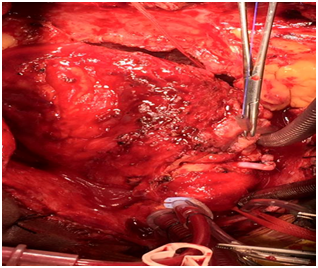

Surgical intervention was done with cardiopulmonary bypass. After Sternotomy, severe dense pericardial adhesion had been seen around the pseudoaneurysdm , adhesion was very carefully dissected, pseudoaneurysm was opened, palpated the stent on RCA, stent had been removed, endarterectomy was done in RCA distal to pseudoaneurysm, 2 small perforation in RCA was repaired by 6-0 polypropylene, RCA proximally and distally ligated with 4-0 polypropylene. Most of the wall of the Pseudoaneurysm had been removed and marsupialization was done. Venous graft was given to distal RCA after long endarterectomy (Figures 1–7).

Figure 4 Pseudoaneurysm opened and removal of stent.

Figure 5 Endarterectomy from proximal and distal coronary artery.

Figure 6 Ligation of proximal and distal coronary artery.

Figure 7 Venous grafts from aorta to distal RCA after in Pseudoaneurysm endarterectomy.